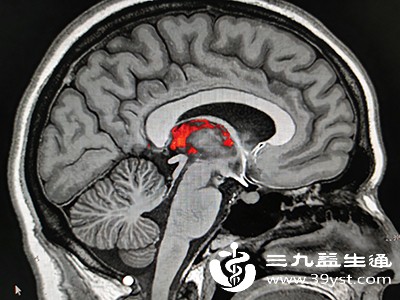

脑出血发生后,脑部血管破裂出血会压迫周围脑组织,导致脑组织缺血、缺氧。随着时间的推移,受压的脑组织会因缺血缺氧而逐渐坏死,且这种坏死是不可逆的。黄金抢救时间内进行有效的救治,能够快速止血、减轻脑组织压迫,最大程度地保护脑细胞功能,降低患者死亡和残疾的风险。有研究表明,在黄金时间内得到及时救治的患者,其生存率和恢复良好的概率要比错过黄金时间的患者高出数倍。

目前医学上普遍认为,脑出血的黄金抢救时间为发病后的4.5小时内,而更精准地说,发病后的1小时内被称为“白金时间”,这段时间内的救治效果最佳。在这个时间段内,及时采取有效的治疗措施,如控制血压、降低颅内压、必要时进行手术清除血肿等,能够显著改善患者的预后。如果超过这个时间,脑组织的损伤可能已经达到较为严重的程度,治疗难度会大大增加,患者恢复的可能性也会降低。